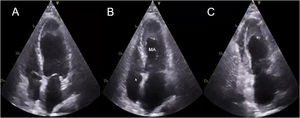

- Imagen de fusión ecocardiográfica-fluoroscópica con la minisonda transesofágica 3D en cardiopatías congénitas pediátricas

- Ramona Ghenghea, Khaled Hadeed, Paul Vignaud-Marighetto, Nicolas Combes, Philippe Acar, Clement Karsenty

- Rev Esp Cardiol. 2026;79:85-8